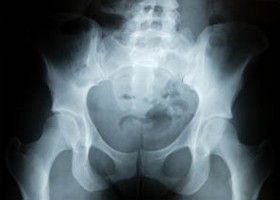

Egy szép napon magunk fejleszthetjük ki új csípőnket! Kutatók szerint a most fém vagy kerámia csípőprotézisre szoruló betegek egy évtized múlva tökéletesen működő szerves pótlást kaphatnak, amelyet saját testükben, személyre szabott fiziológiájukkal növeszthetnek.

A The Lancet folyóiratban megjelent tanulmány arról számol be, hogy a kutatóknak eddig nyulakban sikerült előállítaniuk vállízület protézist. A protézist úgy hozták létre, hogy beültetett biológiai "vázon" növesztettek új porcot.

Dr. Thomas A. Einhorn, a Bostoni Egyetem ortopéd sebész professzora szerint az eredmények óriási előrelépést jelentenek, bár az ízületi gyulladásban vagy degeneratív ízületi betegségekben szenvedő betegek várhatóan csak egy évtized múlva használhatják majd ki az orvosi újítás klinikai előnyeit.

Az eljárás során polikaprolaktonból (biológiailag lebomló műanyag) és hidroxiapatitból (a csontban és a fogakban lévő természetes ásványi anyag) készült keretet ültetnek be a beteg ízület helyére, amelybe transzformáló növekedési faktor béta 3-at fecskendeznek. A gyógyszer serkenti a szervezet saját sejtjeinek (az őssejteket is beleértve) növekedését és porc illetve csontsejtekké alakulását.

A kísérlet során a gyógyszerrel beoltott keretet kapott nyulak gyorsabban tudták használni ízületüket, mint azok, amelyek nem kaptak beültetést. Négy hónappal később a csontfejen új porc képződött, szövődmények és mellékhatások nélkül.

A kutatók elmondták, hogy az eljárást még évekig tesztelni kell, főleg azért, mert egy kísérleti sejtnövekedési faktor felhasználását igényli.